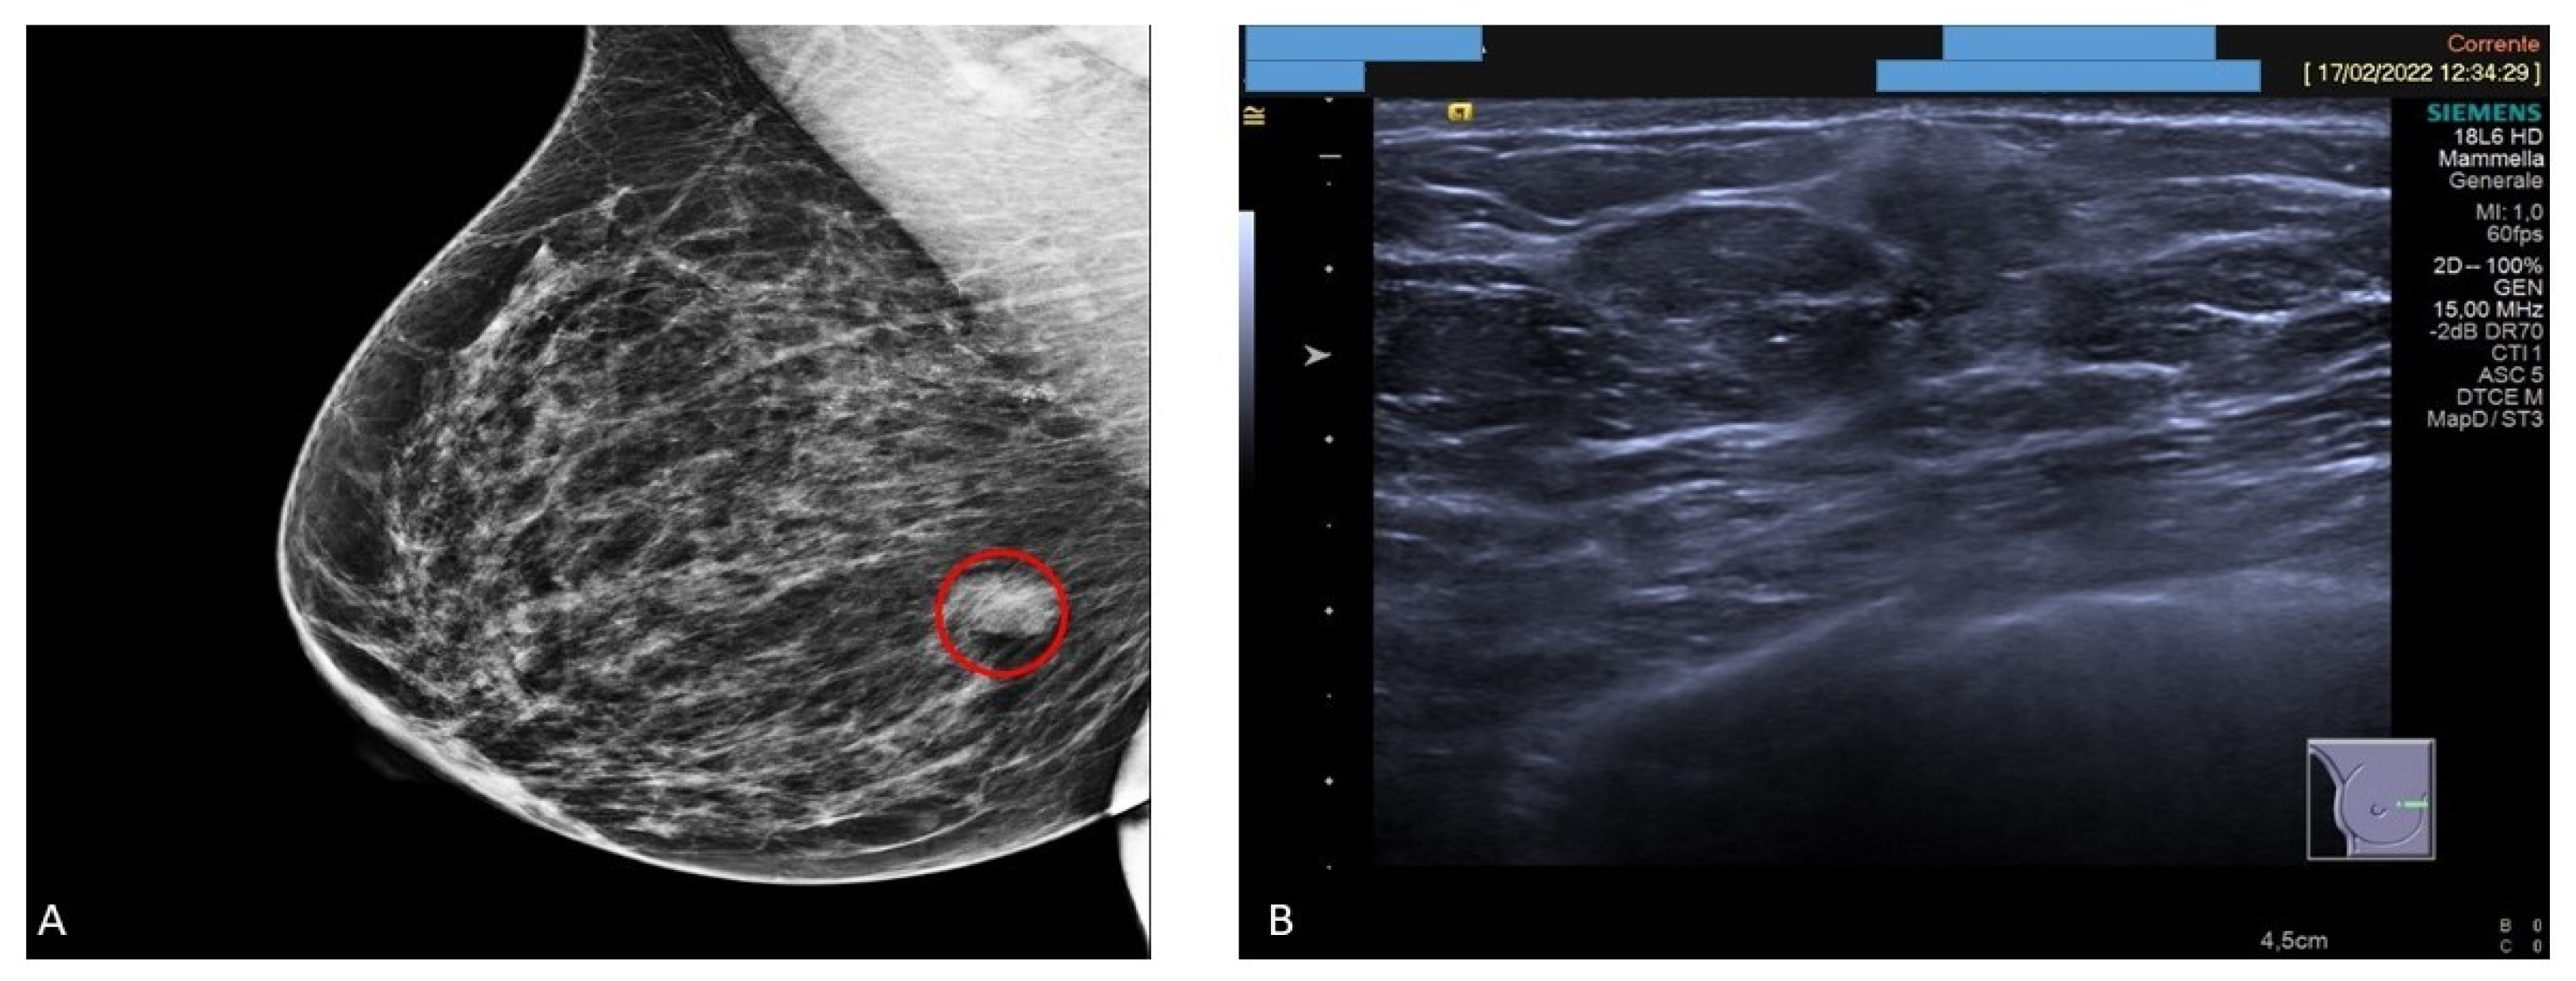

Mammography revealed a 15 mm solid focal asymmetric nodular density in the right internal equatorial location (Figure 1A). Ultrasound examination demonstrated the presence of a firm mass devoid of vascular structures, with an adjacent cyst with an overall diameter of 3 cm (Figure 1B). Serum levels of tumor markers were normal.

Figure 1.

Mammographic and ultrasound features. (A) Mammography examination showing a solid nodule in the internal equatorial location (red circle). (B) Ultrasound examination demonstrating a solid nodule devoid of vascular structures.